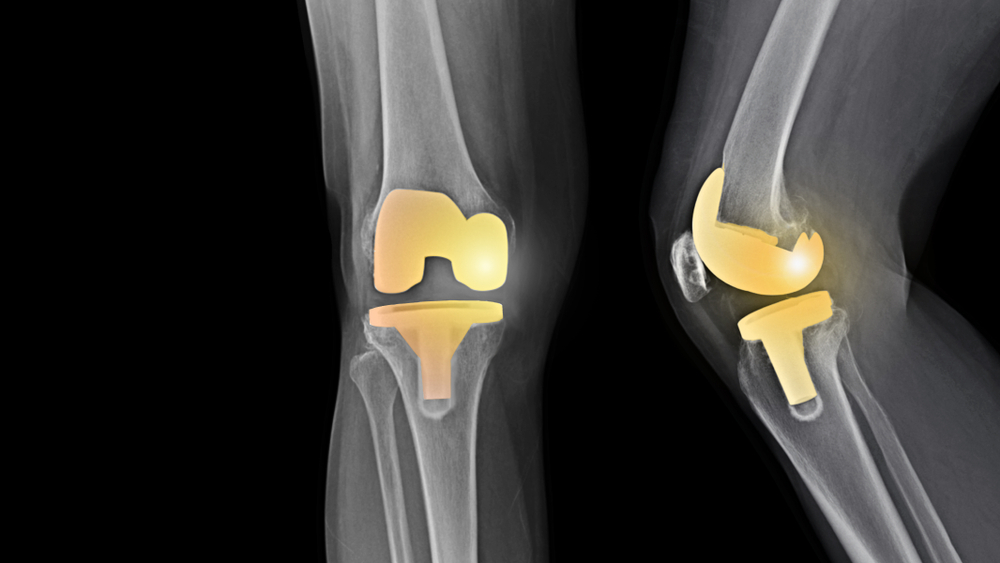

Debido al desgaste de las articulaciones de la rodilla ocasionado por la edad o la artrosis, en ocasiones se debe recurrir a una cirugía de reemplazo total de la articulación, por una artificial conocida como prótesis de rodilla. De esta manera, el cartílago y el hueso dañado se retira aliviando así el dolor intenso.

Una vez que se ha aplicado la anestesia, el cirujano hará una incisión sobre la rodilla, por lo general de 8 a 10 pulgadas d largo. Posteriormente:

Apartará la rótula y cortará los extremos del fémur y la tibia (parte inferior de la pierna) para acomodar la pieza de reemplazo.

Cortará la parte inferior de la rótula con el fin de prepararla para las nuevas piezas que irán pegadas allí.

Fijará las dos partes de la prótesis a los huesos. Una parte irá pegada al extremo del fémur y la otra irá fijada al extremo de la tibia.

Pegará ambas partes a la parte inferior de la rótula. Se usa un cemento óseo especial para pegar estas partes.

Reparará los músculos y tendones alrededor de la nueva articulación y cerrará la incisión quirúrgica.